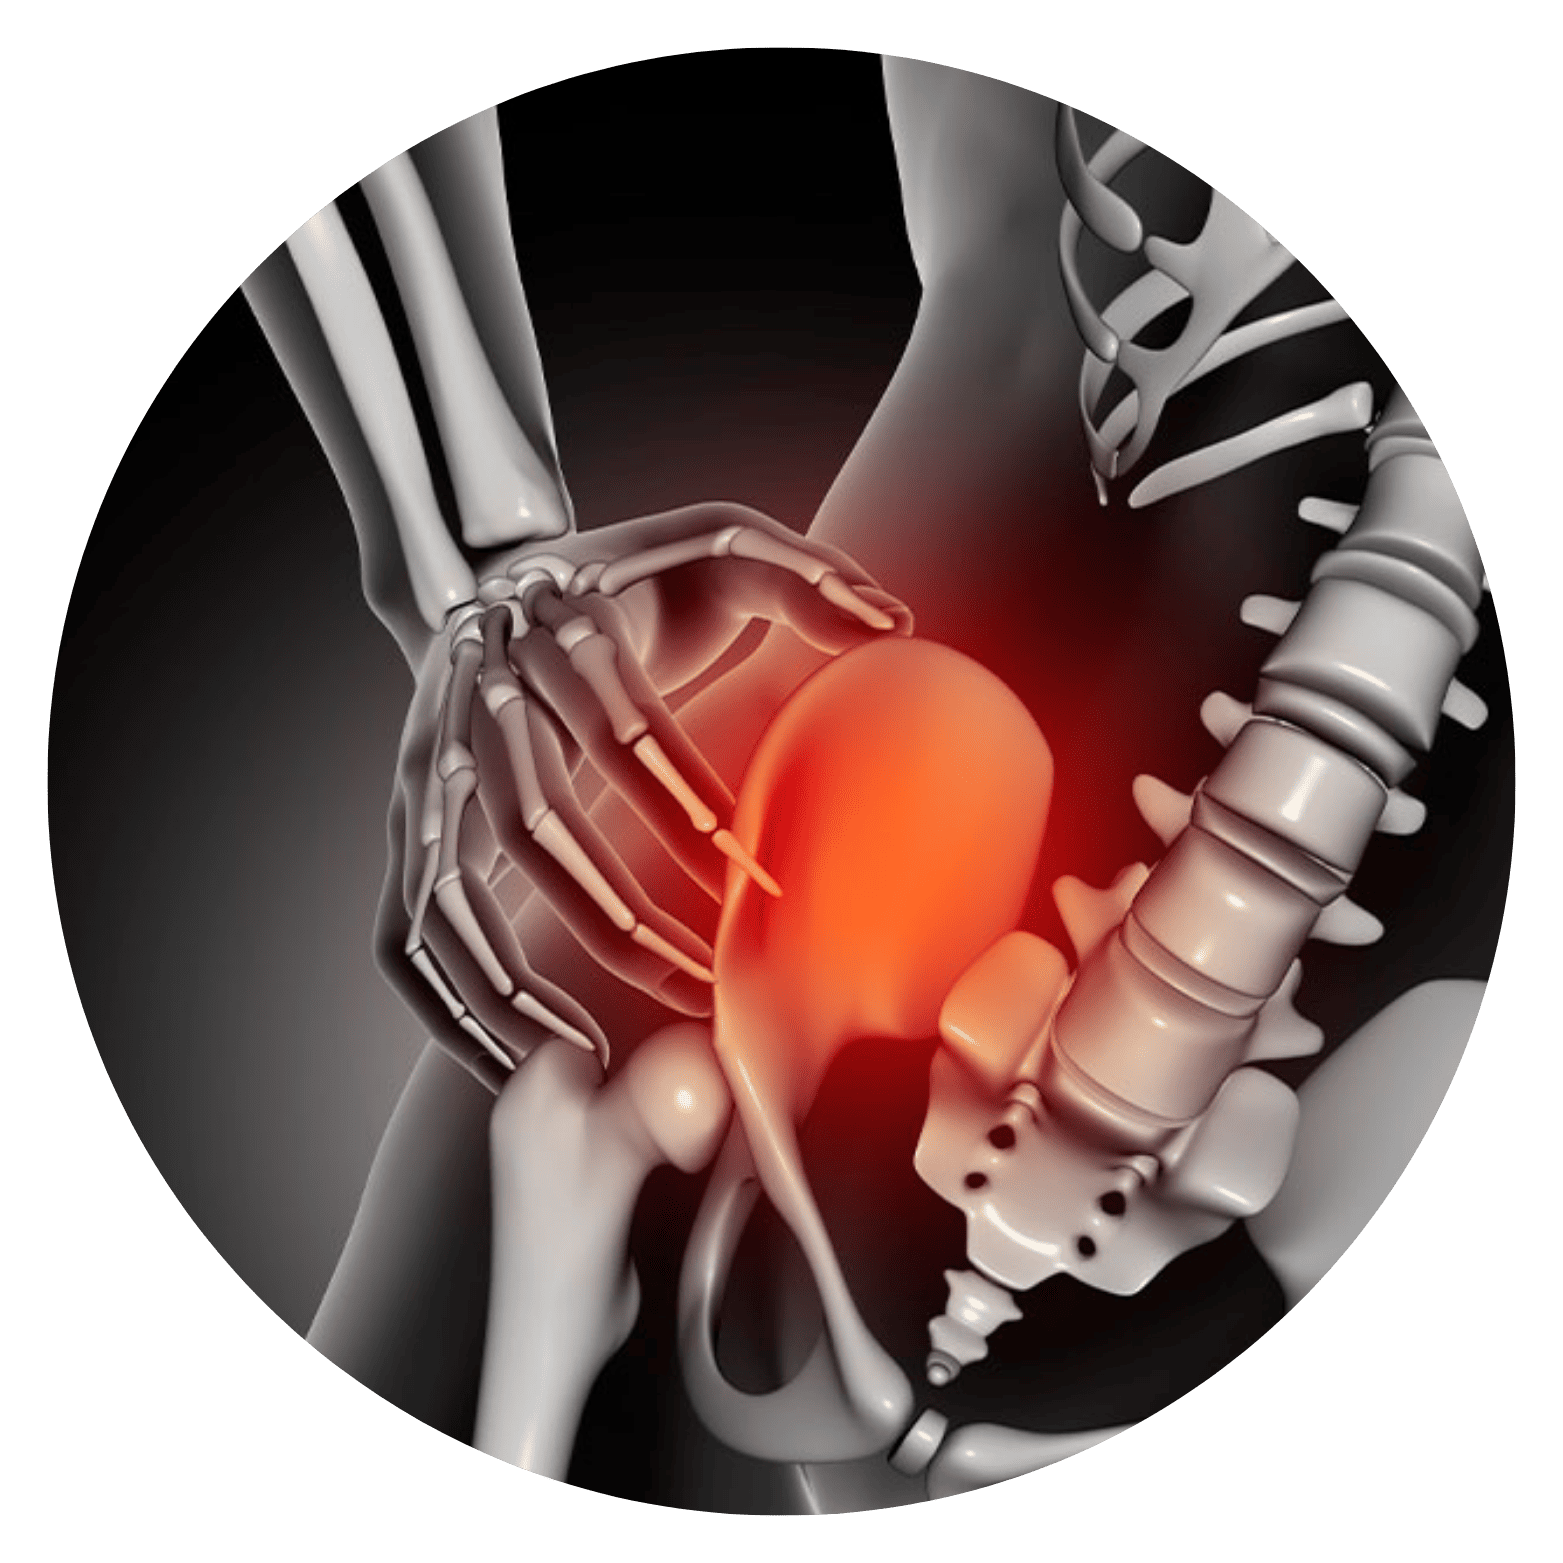

Lesão do Manguito Rotador Sentir uma dor persistente no ombro ao tentar pegar um objeto em uma prateleira alta, ter dificuldade para vestir uma jaqueta